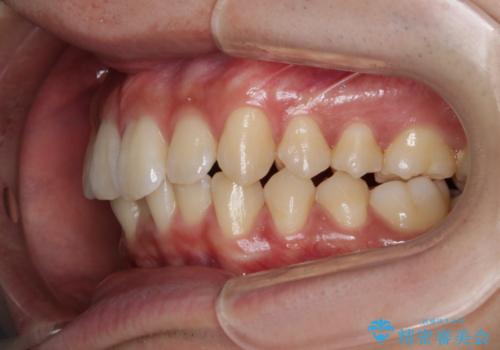

- 前歯のがたつきが気になるとご相談にいらした方です。左の奥歯の噛み合わせのズレも認められたため、インビザライン治療にて改善しました。

主訴である前歯のガタつきだけでなく、奥歯の噛み合わせからしっかり治療したため、治療期間が長めとなりました。患者様ご本人としては治療の途中で一時的にモチベーションが下がったこともあったようですが、最後まで頑張って続けて頂けたことで噛み合わせ及び見た目の改善を行うことが出来ました。